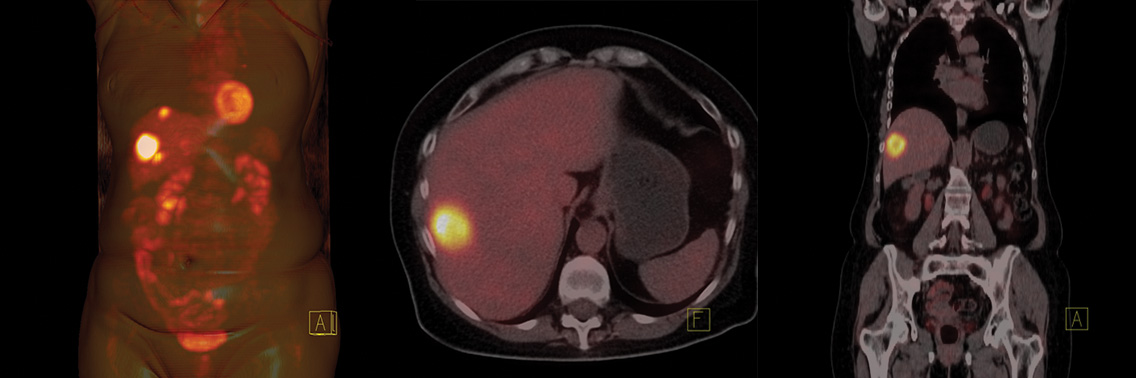

Technika PET jest obecnie podstawową metodą obrazowania molekularnego. Jest stosowana w diagnostyce, określeniu stopnia zaawansowania choroby oraz w monitorowaniu leczenia. Do podstawowych rozwiązań, które jednoznacznie przyczyniły się do rozwoju techniki PET należą wprowadzenie iteracyjnych metod rekonstrukcji obrazów, zastosowanie nowych typów kryształów scyntylacyjnych, wprowadzenie metody PET-CT, opracowanie metody time of flight, a obecnie zastosowanie metody PET-MRI. Zrozumienie zasad techniki PET, jej zalet, a przede wszystkim ograniczeń, jest niezbędne nie tylko dla właściwej interpretacji ostatecznego wyniku przez lekarza, ale również dla optymalizacji parametrów skanowania i oceny źródeł artefaktów przez fizyka/ inżyniera medycznego.

At present, PET is a basic method of molecular imaging. It is applied in diagnostics, for determining the degree of the progress of illness and in monitoring the treatment. To basic answers which explicitly contributed to the development of PET belong introduction of iterative methods for reconstruction of images, applying new types of scintillators, implementing the hybrid PET-CT scanners, developing the method time of flight, and at present, application of PETMRI. Understanding principles of the technique, its limitations and advantages, is essential not only for appropriate interpretation of the final result by the doctor, but especially for the optimization parameters of scanning and the evaluation of sources of artifacts by the medical physics/engineer.